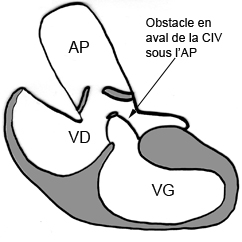

– Sténose pulmonaire : L’IRM aide à discriminer les atteintes valvulaires des obstacles sous ou sus valvulaires dans les cardiopathies congénitales.